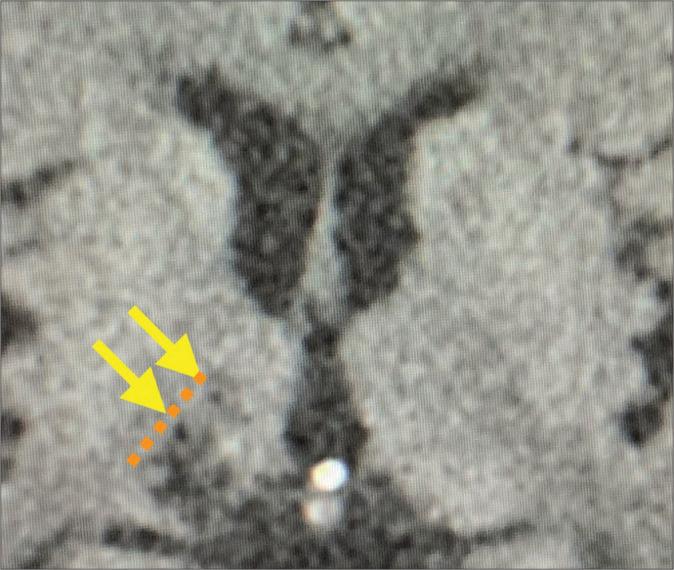

Herein, we present a case report of a patient with Holmes tremor due to thalamic infarction with end-stage pancreatic cancer who underwent successful computed tomography (CT)-guided ventralis intermedius nucleus (Vim) thalamotomy as palliative care.

A 78-year-old man with gradually worsening involuntary movements on the left side of his body 2 years after a right thalamic infarction was referred to our institute. He had a history of chronic atrial fibrillation for which he was implanted with a cardiac pacemaker not compatible with magnetic resonance imaging. He also received adjuvant therapy for pancreatic cancer. As the involuntary movements interfered with his daily life, the patient elected for neurosurgical treatment despite having terminal cancer. Although the prognosis for pancreatic cancer was considered to be more than 6 months at the time of surgery, we performed CT-guided Vim thalamotomy under local anesthesia without pulse generator implantation considering the patient's general condition. The involuntary movements of the left side of the body reduced following surgery, thus improving his quality of life (QOL). However, 6 months after thalamotomy, the patient died of pancreatic cancer.

在此,我们报告一例因丘脑梗死合并晚期胰腺癌导致霍姆斯震颤的患者,该患者接受了成功的计算机断层扫描(CT)引导下的腹中间核(Vim)丘脑切开术作为姑息治疗。

一名78岁男性,在右侧丘脑梗死后2年,身体左侧的不自主运动逐渐加重,被转诊至我院。他有慢性心房颤动病史,为此植入了与磁共振成像不兼容的心脏起搏器。他还接受了胰腺癌的辅助治疗。由于不自主运动干扰了他的日常生活,尽管患有晚期癌症,患者仍选择接受神经外科治疗。尽管手术时胰腺癌的预后被认为超过6个月,但考虑到患者的一般状况,我们在局部麻醉下进行了CT引导下的Vim丘脑切开术,未植入脉冲发生器。手术后,身体左侧的不自主运动减少,从而改善了他的生活质量(QOL)。然而,丘脑切开术后6个月,患者死于胰腺癌。